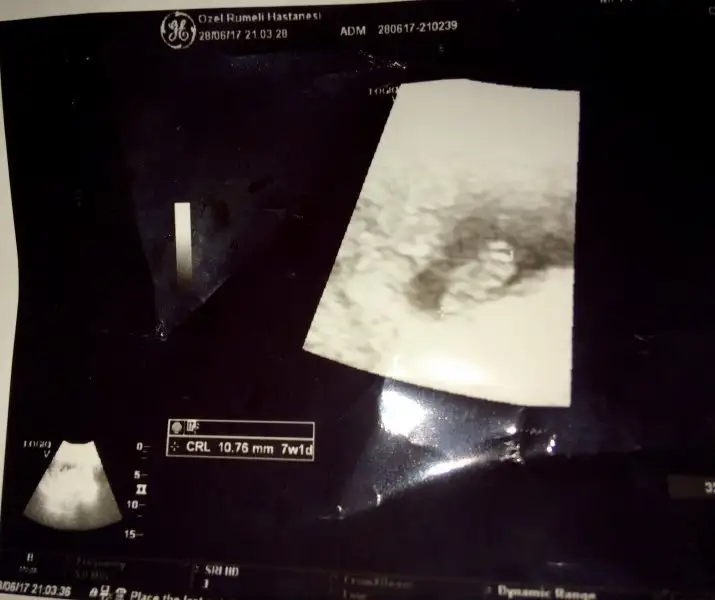

Kızlar 7+1 dedi doktor gittik ben 8 hafta bekliyordum demekki yanlış hesaplamışım :)